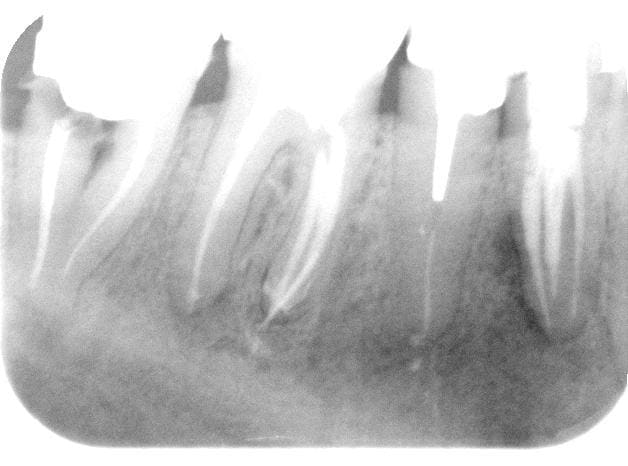

petit cas, commencé il y a quelques années.

C'est de l'ortho mais je suis omnipraticien.

Le cas ou j'ai le plus galéré ( classe 3 et surtout 43 incluse ), mais qui m'apporte beaucoup de satisfaction.

fille d'un ami en plus!